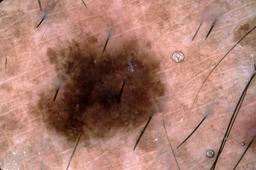

{

"age_approx": 80,

"anatom_site_general": "head/neck",

"concomitant_biopsy": true,

"dermoscopic_type": "contact non-polarized",

"diagnosis_1": "Malignant",

"diagnosis_2": "Malignant melanocytic proliferations (Melanoma)",

"diagnosis_3": "Melanoma Invasive",

"diagnosis_confirm_type": "histopathology",

"image_type": "dermoscopic",

"lesion_id": "IL_0134474",

"melanocytic": true,

"patient_id": "IP_4497472",

"sex": "male"

}